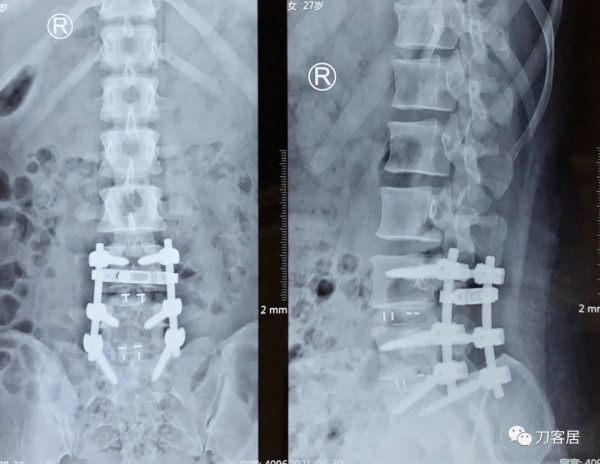

圖9. 20210830術後6天拍攝的腰椎正側位X線片,可見腰5雙側椎板均已切除減壓,所以, 這個手術應該是做的腰4-骶1後路全椎板切除減壓,腰4-骶1椎間融合器植骨融合, 每個間隙兩枚融合器,腰4-骶1後外側植骨融合內固定術。應該是典型的PLIF手術。

圖10. 20210831術後7天拍攝的腰椎側位X線片及右側股骨正側位X線片,顯示術後內固定位置良好,但不知道為啥當時給拍了右側股骨正側位X線片,也許可能術後右大腿部有比較明顯的疼痛吧。應該是8月30日到31日這兩天,患者的下肢症狀應該有反覆。否則不應該做腰椎手術,拍股骨X線片的。